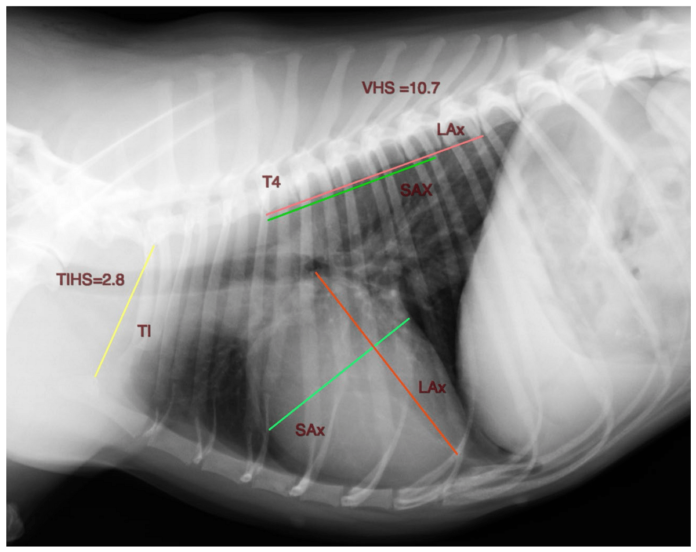

“A todos los perros analizados se les realizó un estudio ecocardiográfico para valorar las dimensiones del ventrículo y del atrio izquierdo, así como una proyección radiográfica torácica lateral derecha. A la mayoría de los pacientes también se les tomó una proyección ventrodorsal lateral izquierda”, explica David Marbella, autor principal del estudio e integrante del Área de Cardiología y Cirugía Cardiovascular del centro. “La longitud de la entrada torácica la definimos como la distancia más corta medida entre el borde craneodorsal del manubrio esternal, en su punto más alto, y el borde craneoventral del cuerpo de la primera vértebra torácica”, añade.

Para medir el tamaño cardíaco utilizando el protocolo TIHS, para este estudio, que tuvo una duración de un año y medio, se seleccionaron 122 perros de más de un año, sin signos clínicos de enfermedades cardiovasculares o respiratorias y sin antecedentes de cirugía de cuello o tórax. Además, no se excluyeron perros con malformaciones vertebrales torácicas. Todos ellos eran de las razas más representativas en el centro canario: Chihuahua, Bulldog Francés Golden Retriever, Labrador Retriever, Yorkshire Terrier, Dálmata, Beagle, Perro de Agua Español, entre otras.

Tras analizar los resultados, se concluyó que el TIHS es un método sencillo, directo, fiable y reproducible para medir la silueta cardíaca de un perro en una proyección torácica lateral derecha. Con un valor medio de 2,86 y un intervalo de confianza de 2,81-2,91 (95%), se sugiere un valor TIHS ≤ 3,2 como límite superior para definir el tamaño normal del corazón de un perro sano.